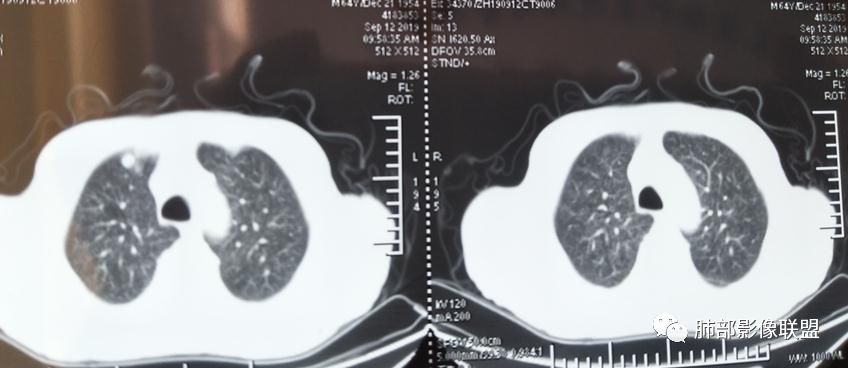

2019年9月12日CT(外院片,手机拍摄)

8月份就有弥漫细小结节

9月外院片也有弥漫细小结节

左上纵隔旁病灶存在

大小、分布均匀,边缘清楚

细小结节,弥漫,撒米粒样——血道来源

部分可见分支状

边缘稍平直

毛刺细弱

还是支持结核

血道来源的病灶,均匀、细微,而且部分有分支状,都符合粟粒型肺结核